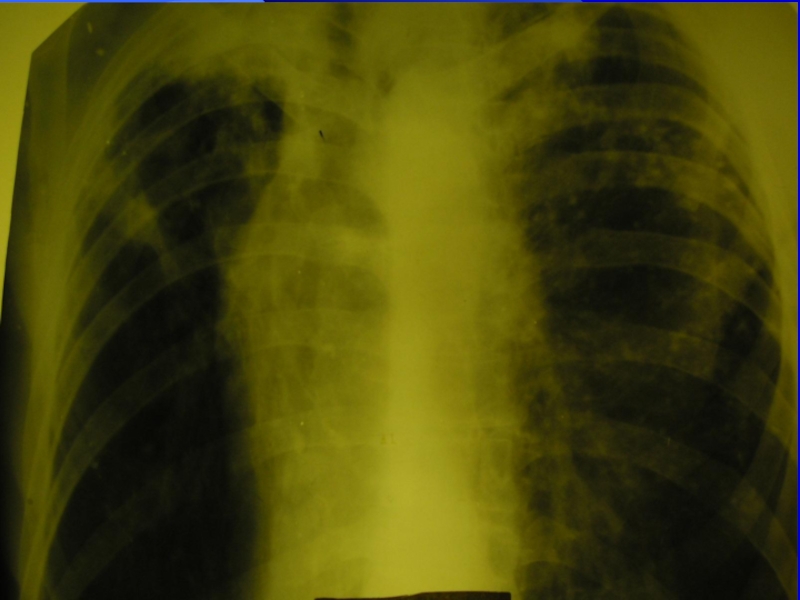

Слайд 28Хронический диссеминированный туберкулез

При хроническом диссеминированном туберкулезе преобладает продуктивная тканевая

реакция. При этом уплотненные и более крупные очаги располагаются в

верхних отделах легких, меньшей величины – в нижних. Наряду с очагами в наружно задних отделах верхних долей имеются рубцы.

Могут быть штампованные каверны, петрификаты.

Характерен диффузный сетчатый склероз, эмфизема.

Обычно формируется хроническое легочное сердце.